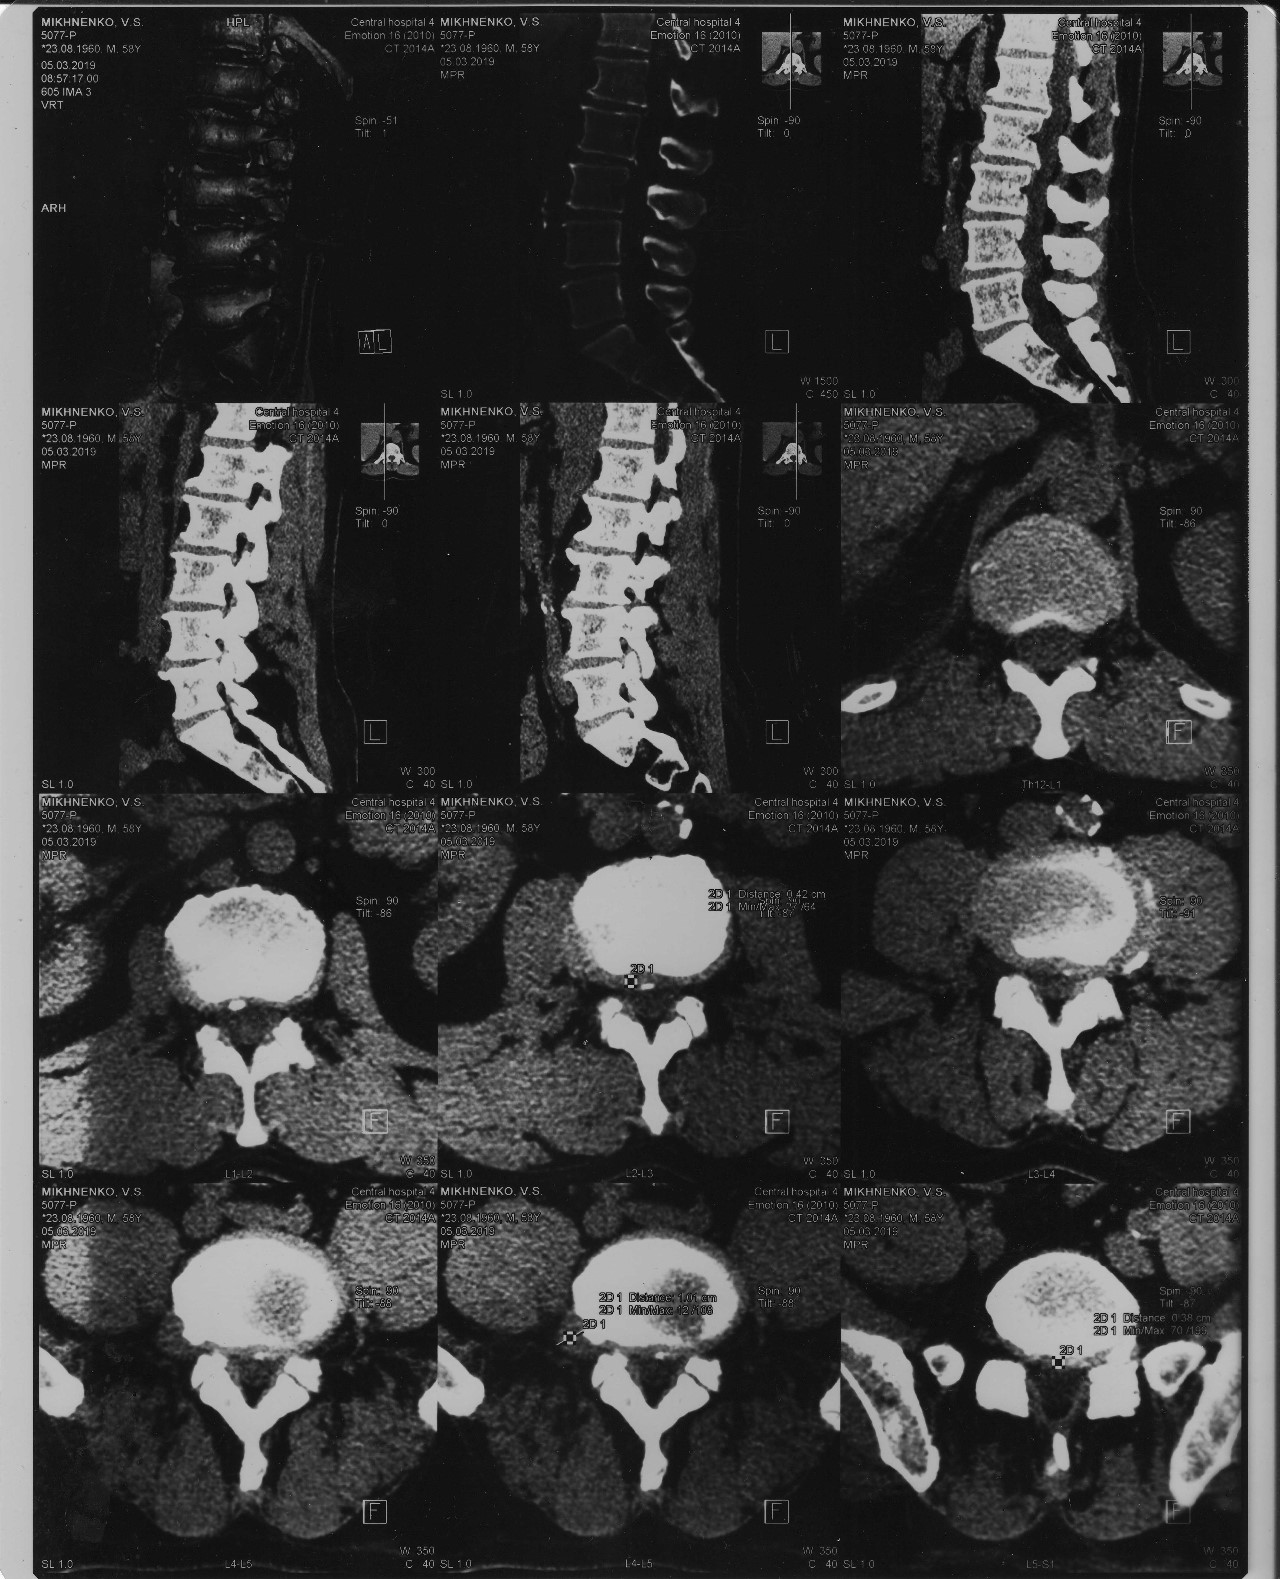

Мрт картина дегенеративно дистрофических изменений пояснично крестцового отдела позвоночника